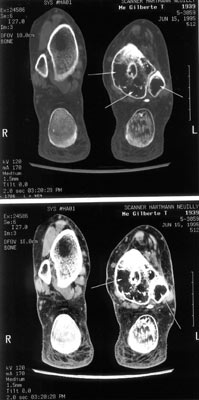

Pain happens during walking more and more frequently either during daytime or at night. Pain increases and is no longer relieved by pain-killer. The skin is warm and pink. No signs of infection. The joint is stiff and the foot mobile. The CT scan reveals a severe demineralization (arrows) either on the tibia and the fibula too. If it became necessary by time, in the future, to fix this joint, the technical problem will be difficult because of that bone loss. A graft will be necessary for sure. |

Another view of the tibia (CT scan)